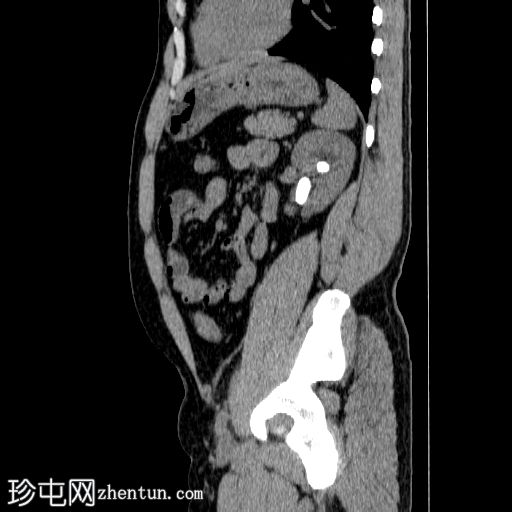

矢状位

平扫

左侧肾盂内可见一鹿角状结石,延伸至肾盏系统,平均CT值约为1200 HU。

右肾可见数枚微小结石,最大一枚位于肾下盏,直径约2 mm。这些结石未引起任何梗阻性改变。